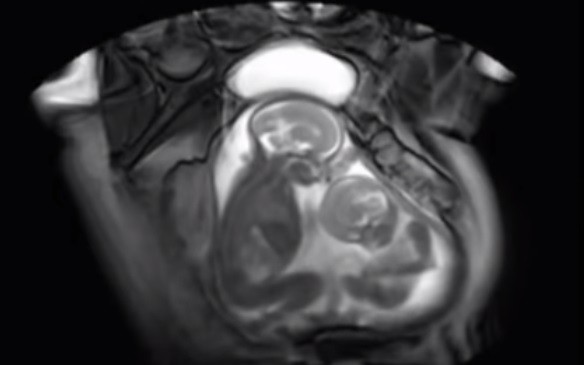

La ecografía viral que muestra a dos bebés “peleando” en la panza de su madre

Las divertidas imágenes muestran a dos pequeñas gemelas “luchando” entre sí dentro de la panza mientras la madre se realizaba una ecografía y las redes estallaron.

ecografía gemelos

(Foto: Imagen ilustrativa)

Según el padre, sus hijas compartían el mismo saco amniótico y placenta. Este tipo de casos es conocido como gemelos monoamnióticos monocoriales o gemelos Mo-Mo y es uno de los embarazos de gemelos de mayor riesgo posible.

Tal como afirman los especialistas, solo hay un 50% de probabilidades de que los bebés sobrevivan después de las 26 semanas. El principal riesgo se basa en que los cordones umbilicales, que están separados, se pueden enredar y anudar, generando un flujo sanguíneo deficiente en uno o ambos bebés.